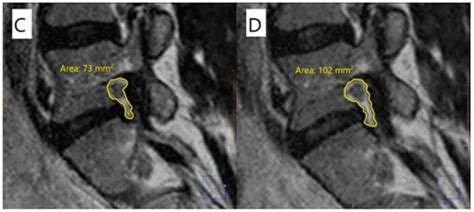

mdpi.com